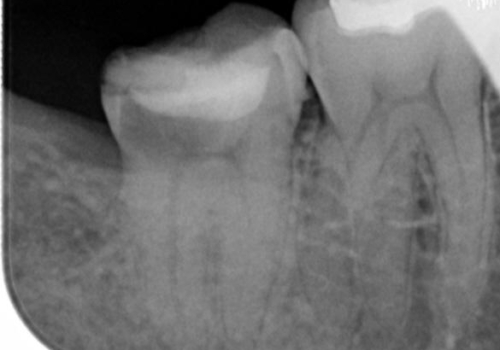

左右の第二大臼歯は虫歯がひどく抜歯が必要な状態でした。

また、左下の第一大臼歯は歯が内側から吸収してしまう状態(外部吸収)が生じており、患者様と相談の上抜歯しました。